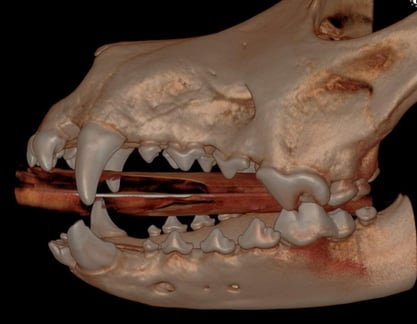

Henry, a 4-year-old neutered male Labrador Retriever, was referred for evaluation due to a broken lower left canine tooth (304), suspected to have occurred several months prior as a result of an accident.

Below: 3D Overview before procedure: (left and right)